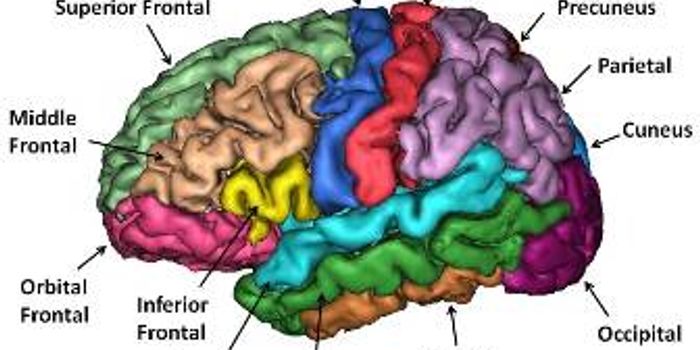

APR 03, 2015NeuroscienceExtensive research has been conducted about the 300 different kinds of neurons in the brain and their function, but this ...

JUL 17, 2015NeuroscienceWhat causes autism? Is there something physical that accounts for behavioral differences?

APR 08, 2015NeuroscienceIndiana University researchers have found that broken communication in a specific part of the brain plays a role in the ...

APR 09, 2015NeuroscienceA new study by UNC researchers, based on MRI brain scans of 152 infants, found disruptions in functional connectivity wi ...

NOV 21, 2014NeuroscienceResearchers from Ben-Gurion University of the Negev (BGU) and Carnegie Mellon University have shown that the brain anato ...

MAY 11, 2017NeuroscienceThe brain is an incredibly complex organ. It powers and controls every bodily function, processes thoughts and memories, ...